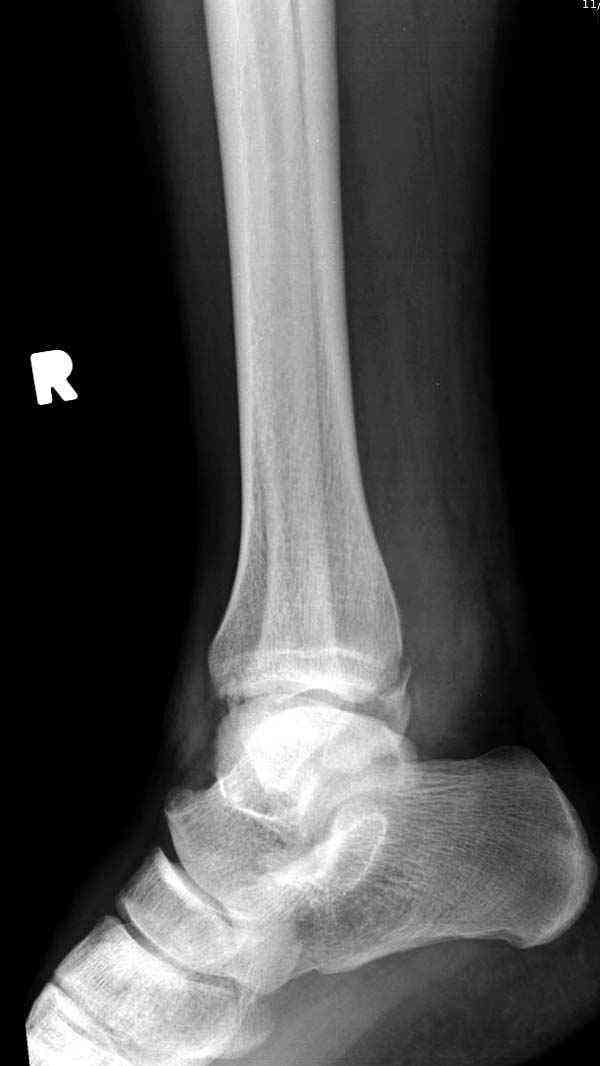

Внутренняя лодыжка

Имя     : 1 Med mal fx Hook plate 0.JPG

Имя     : 2 Med mal fx Hook plate 00.JPG

Имя     : 3 Med mal fx Hook plate 000.JPG

Имя     : 4 Med mal fx Hook plate.JPG

Имя     : 8 Med mal fx Hook plate mortise.jpg

Имя     : 9 Med mal fx Hook plate.JPG

Имя     : 10 Med mal fx Hook plate.jpg